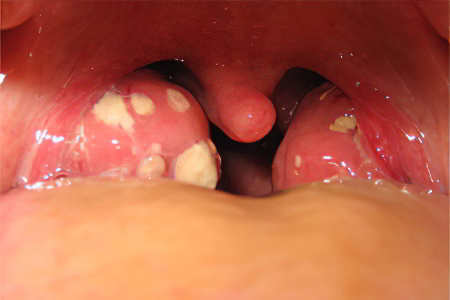

- Лакунарная форма — вовлекаются лакуны миндалин. Лакуны — это глубокие извивающиеся каналы, которые обычно очищаются от микробов самостоятельно. При снижении местного иммунитета их способность к самоочищению нарушается, что приводит к накоплению налёта и гнойных масс.

- Гнойное содержимое в лакунах.

- Налёт на миндалинах.

- Воспаление фолликулов миндалин.